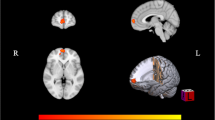

Regarding the nodal DC, compared with the NMM group, the MRM group had higher a degree mainly in the insula, inferior frontal gyrus (IFG), and orbital gyrus (OrG), and a lower degree in the thalamus and BG. After controlling for the demographic and clinical characteristics, group differences between MRM and NMM patients were no longer present in the insula, but they persisted within the IFG, thalamus, and BG (Fig. 1; Table 3). Additionally, we further investigated the association between the above regions and HIT-6 scores using Pearson correlation analysis. We found that the DC in the IFG of MRM patients was negatively correlated with their HIT-6 scores (p = 0.012, r = −0.349; Fig. 2), but an equivalent correlation was not found in the NMM group.

Significant between-group differences in the nodal degree centrality between the MRM and NMM groups. (a) Significant differences in the nodal degree centrality between the two groups before regression analysis. (b) Significant differences in the nodal degree centrality between the two groups after regression analysis. Regions colored in red have a significantly higher nodal degree for the MRM group, while regions colored in blue indicate a lower degree for the MRM group. Data shown were visualized with the BrainNet viewer (www.nitrc.org/projects/bnv). Abbreviations: BG, basal ganglia; IFG, inferior frontal gyrus; INS, insula; MRM, menstrually-related migraine without aura; NMM, non-menstrual migraine without aura; OrG, orbital gyrus; Tha, thalamus

Taken together, after controlling for the demographic and clinical characteristics, these results indicate the group differences in nodal degree between the MRM and NMM patients were no longer present in the insula, while those in the IFG, thalamus, and BG persisted. Nodal centrality in the IFG of MRM patients was negatively correlated with their HIT-6 scores (p < 0.05).